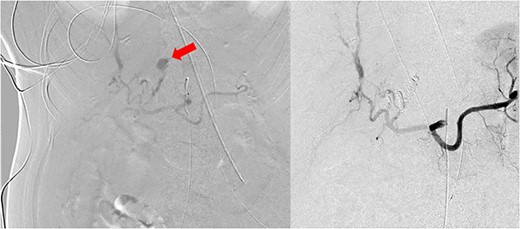

A 61-year-old female with a past medical history of hyperlipidemia, hypertension and diabetes presented to a referring facility emergency department with abdominal pain, nausea, vomiting, diarrhea and headache for 2 days. The patient did not take anticoagulants or antiplatelet therapy. She had no history of trauma. A computed tomography (CT) scan with intravenous contrast was obtained, which demonstrated diffuse colonic wall thickening. Her initial laboratory findings were within normal limits, and she was ultimately discharged with a diagnosis of nonspecific colitis. Later that same evening, the patient represented to the referring facility emergency department with worsening of her abdominal pain. Shortly after arrival, she became obtunded, required intubation and had a significant decline in her hemodynamics. Laboratory analysis revealed a hemoglobin of 8.3 g/dL (15.9 g/dL at the time of primary evaluation), a lactic acid of 20 and a pH of 6.8. An emergency CT angiogram was obtained. This revealed large amounts of intra-abdominal fluid consistent with hemoperitoneum that was new from the previous scan. It also demonstrated an arterial enhancing 13 mm central left hepatic lesion that represented a hepatic pseudoaneurysm (Fig. 1). Blood product administration was initiated, and the patient was transferred to our facility for further management.

Imaging showing initial CT scan (left) and repeat CT angiogram (right) several hours later. Red arrow is identifying left HAP.